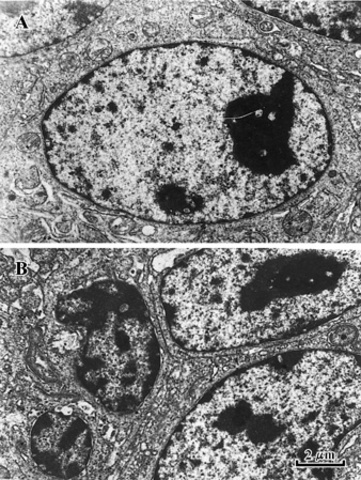

Brown made his discovery by looking at cells of orchids through a microscope. He discovered the nucleus of a cell. This disproves the previous model because Brown shows that even though extremely tiny, cells contain a nucleus.